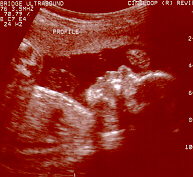

Jolie's Face

Front view of Jolie's Face on the right.